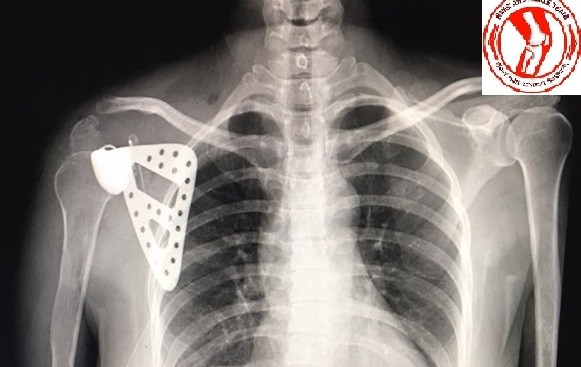

Bệnh nhân được thay xương bả vai.

Qua năm ngày điều trị, hiện tại cô Th đã hoàn toàn khỏe mạnh, đã cử động được phần cẳng tay và bàn tay bình thường, vết mổ hoàn toàn khô, không có dịch. Phim chụp X-quang cho thấy xương bả vai nhân tạo hoàn toàn đúng vị trí giải phẫu, chưa phát hiện các biến chứng nghiêm trọng nào.